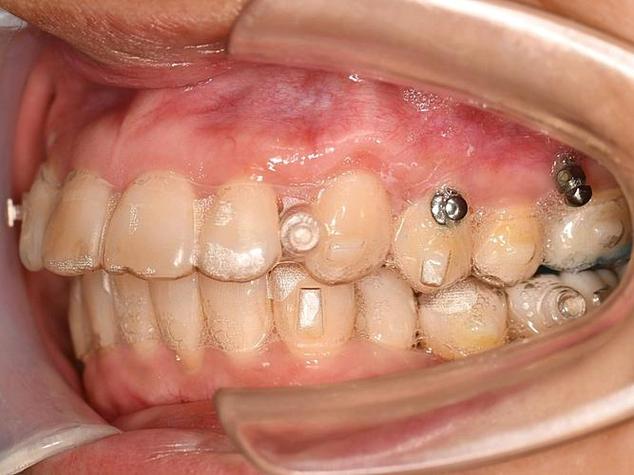

- 器械准备: 医生会使用专门的器械,通常是一个类似小扳手或螺丝刀形状的专用取钉器(有时也可能用持针器或蚊式钳,但专用工具更常见)。

- 医生会用器械稳稳地夹住或套住支抗钉的头部(暴露在牙龈表面的部分)。

- 医生会轻轻地、稳定地向逆时针方向旋转,支抗钉通常是自攻螺纹设计,取下时就是反向拧出。